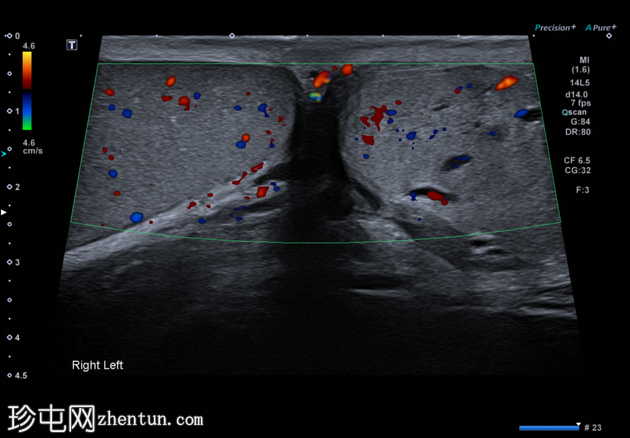

纵切面

左侧睾丸内血管呈迂曲管状扩张,Valsalva动作可见充血。

典型的管状睾丸内精索静脉曲张超声表现,Valsalva动作可见扩张的睾丸内静脉充血。睾丸内精索静脉曲张常与同侧儿童时期睾丸固定术相关,本例患者即曾接受过该手术,且多见于左侧,本例亦属如此。